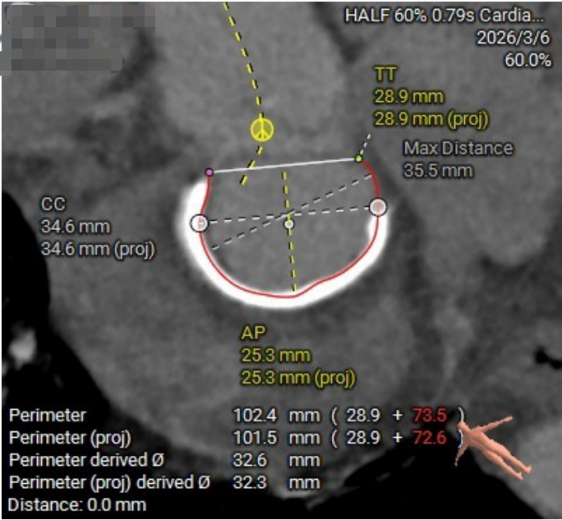

二尖瓣瓣环测量

03.jpg

04.jpg